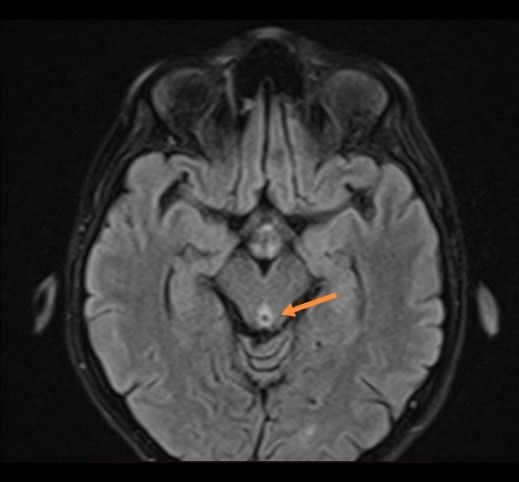

Control MRI of the brain was performed. This follow-up showed a resolution of previously bilateral hyper intense signals regions on T2/FLAIR sequence, with progressive reduction of hypersignal changes of bilateral thalamic regions of restricted diffusion (Figure 3).

| Figure 3. Presentation of reduction of hypersignal changes of bilateral thalamic regions on T2 FLAIR on MRI. |